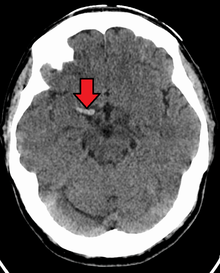

Cerebral venous sinus thrombosis (CVST) is a rare form of stroke which results from the blockage of the dural venous sinuses by a thrombus. Symptoms may include headache, abnormal vision, any of the symptoms of stroke such as weakness of the face and limbs on one side of the body and seizures. The diagnosis is usually made with a CT or MRI scan. The majority of persons affected make a full recovery. The mortality rate is 4.3%.[10]